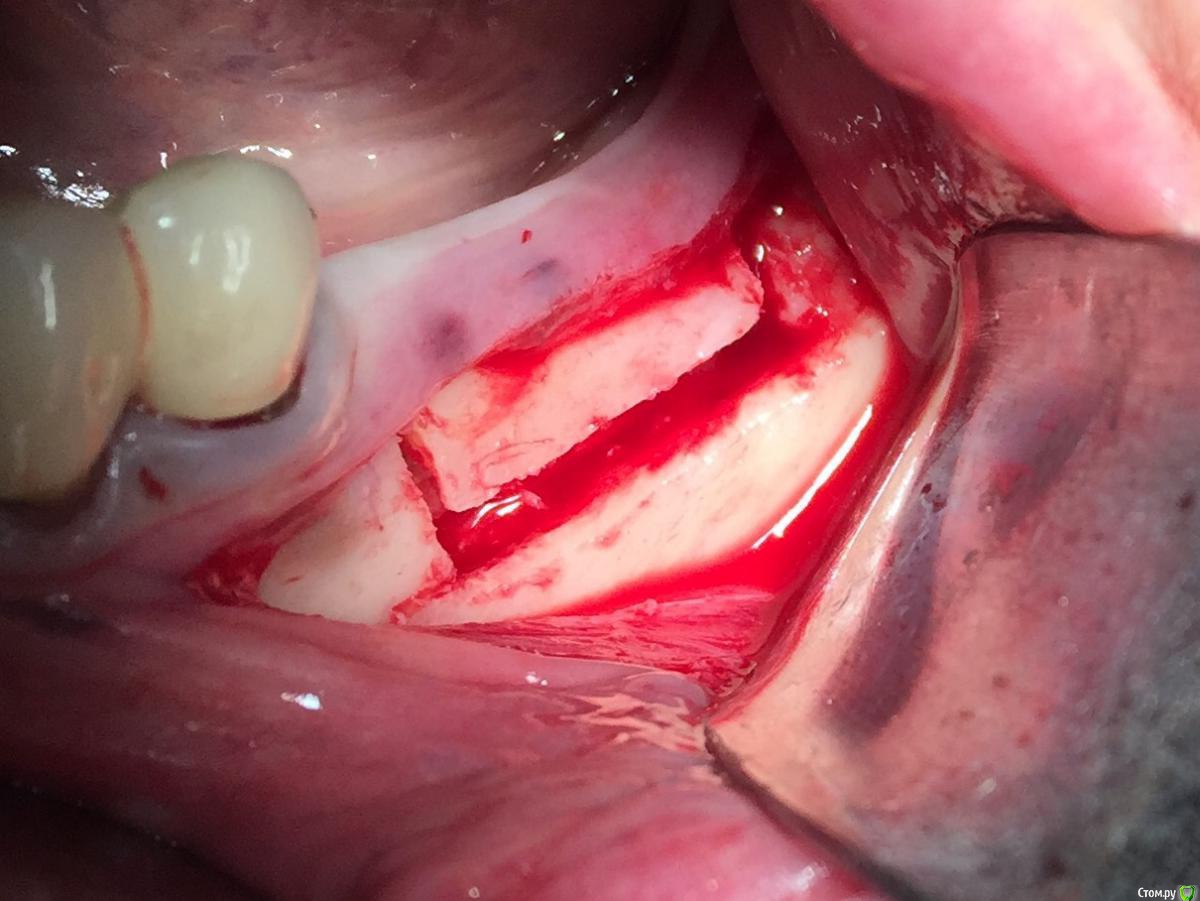

Глеб Митрофанов Опубликовано 16 января, 2016 Автор Поделиться Опубликовано 16 января, 2016 Винты 1,5 мм самосверлящие,Конмет?Длина какая? L пластины длинные? Да , винты 1,5 мм самосверлящие конметовские длина верхние 5 мм , нижние 4 мм , пластины не длинные , по одному сегменту отпилил еще 1 Ссылка на комментарий

Глеб Митрофанов Опубликовано 19 января, 2016 Автор Поделиться Опубликовано 19 января, 2016 Верхние винты насквозь через SP и в свою кость? Как горизонтальный распил делаете, пальцем с язычной, тактильно? Пилите УЗ?И есть ли снимок до?Верхние винты в свою кость , распил делал УЗ , язычно контроль пальпаторно , да и чувствуется , что прошёл язычную кортикалку . Снимок до конечно есть . Ссылка на комментарий